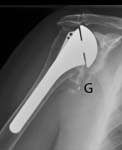

Radiographs include an anteroposterior view in the plane of the scapula an axillary view and a full humeral view all of high quality. Here is an AP view and an axillary view showing a glenoid component that has completely loosened from the bone and is floating free within the joint (two white dots near the letter "G"). [See Figures 19 20]

In cases of instability, examination under fluoroscopy may be useful. The radiographic evaluation must confirm the type and size of components, their position, and the nature of their fixation to bone. The preoperative plan must include a definitive plan for removal of the glenoid and humeral components, should this prove necessary, as well as a plan for reconstruction of the humerus and the glenoid after prosthesis removal. If removal of a cemented humeral component may be necessary, it is essential to have a full set of cement removal tools, a high speed saw capable of cutting a prosthetic stem fluoroscopy, and long stem prostheses of all possible sizes. The possible need for bone and tendon graft is also anticipated.